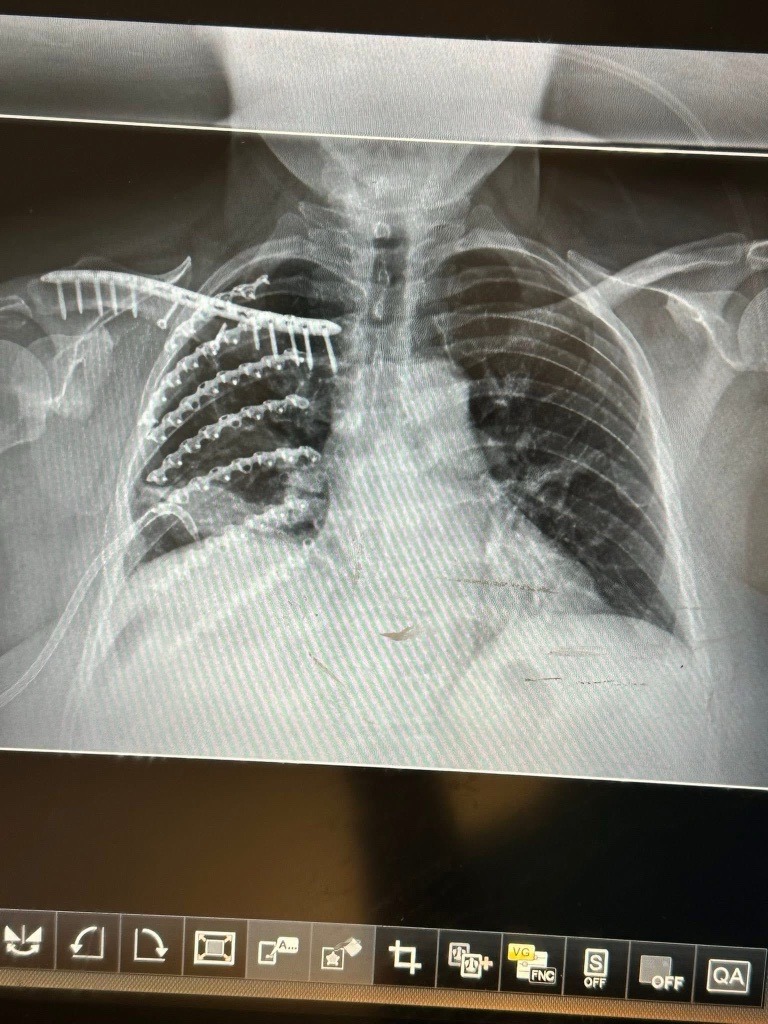

Hello- we are Jessy's people- as are all of you. We are not sure how much you know of her story, which we will share here. On Wednesday May 7, 2025, Jessy was in a motorized scooter accident. Jessy is not sure what happened. However, this accident left her with multiple injuries and ongoing complications. Her original injuries have been a broken collar bone (now plated with screws), broken shoulder blade, 7 broken ribs (plated with screws) and a broken bone that is part of her knee. She also has had a lacerated spleen, liver, and gall bladder. After discharging home from these injuries, she was readmitted about two weeks later with sepsis from a part of her liver that was dying and infected. During this admission, she had part of her liver and all of her gall bladder removed. Due to the infection, she had two abdominal drains placed to help remove the infection. One drain was removed within one week and the other remains. Two weeks after her 2nd admission, Jessy was admitted for a third time with sepsis once again. This time, they could not find the source of the infection, however she was treated with antibiotics and sent home. She is currently at home and working on healing. As of late July 2025, Jessy owes $10,000 in bills after insurance coverage. We know she has not received all of her bills from her first visit and has not seen any of her bills from the 2nd and 3rd visits. In addition, Jessy has multiple in home visits with health care providers on a weekly basis, which she will also receive bills for.